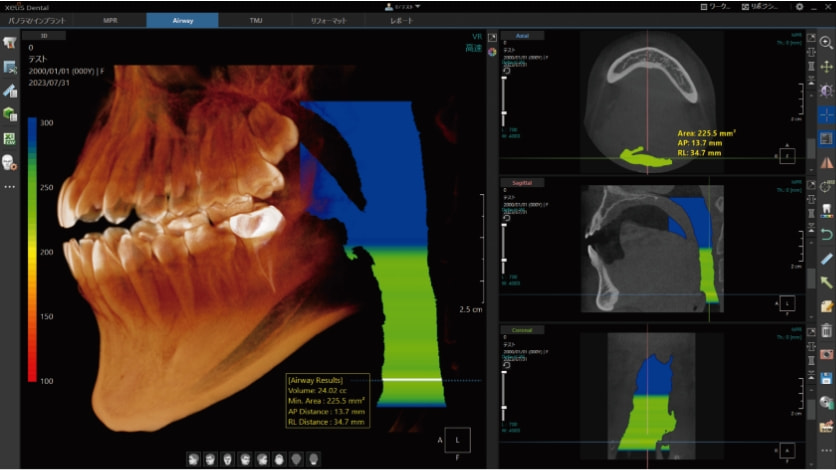

CT画像専用ビューアーソフト「 XelisDental(ゼリスデンタル )」

Pano/Implant、MPR、TMJの各種解析ツールをタブで切替できます。

タブの切替のみで、ツールアイコンが変化する為、迷わず操作が可能です。

VOI , Cube機能 / VRのスカルプト機能

MPR表示では、局所拡大表示も可能。

軸の回転に加え、スライス厚の変更やボリュームレンダリング画像のスカルプト機能も搭載。

VOIやCube機能で、解析部位を絞り込んで表示する事ができます。

歯科領域で必須とされる各解析ツールを搭載。

歯列弓や下顎管の抽出等のアナログな作業を軽減する、各種オート機能を搭載。

オートアーチ機能

任意のアキシャル画像をクリックするだけで、自動的にパノラマ画像が作成できます。

それと同時に、クロスセクショナル画像も作成されます。

下顎管の抽出

下顎孔とオトガイ孔の最小2クリックで、下顎管の抽出が可能です。

エアウェイ(気道領域)の抽出

2クリックで気道領域を抽出。

最も狭い箇所の位置、面積、縦横の長さを自動で表示します。

TMJの左右同時検出

左右どちらかの下顎頭を指定すると、反対側の下顎頭を自動的に検出します。